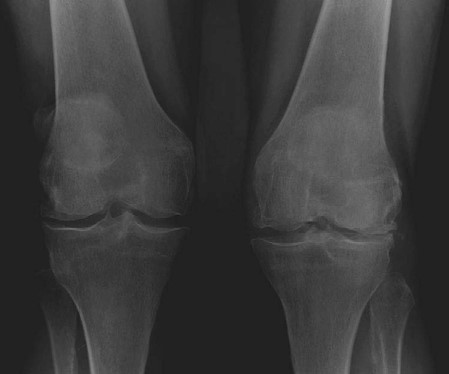

EXAMINER : This is a radiograph of a 72-year-old lady complaining of pain and gradual deformity of both knees. She has been referred to your clinic to be considered for total knee arthroplasty. What can you see? (Figure 3.1.) CANDIDATE : These are weightbearing anteroposterior ( AP ) views of a 72-year-old lady demonstrating narrowing of joint spaces with bone-on-bone contact in the lateral compartments of both knees. There is early arthrosis affecting the medial compartments of both knees. There is moderate valgus deformity. EXAMINER : What conditions are associated with this pattern of joint disease? CANDIDATE : The valgus deformity of the knee with arthritis is commonly seen in women and in inflammatory joint conditions such as rheumatoid arthritis. It can also occur in primary osteoarthritis, overcorrection of high tibial osteotomy (HTO), post-traumatic arthritis following lateral meniscectomy and osteonecrosis. EXAMINER : What are the perioperative considerations for total knee arthroplasty in valgus knee? CANDIDATE : The preoperative assessment should include a thorough history and examination to establish if there are any predisposing factors such as rheumatoid arthritis and the success of non-surgical management. The competency of the knee collateral ligaments and degree of deformity correction should be assessed in order to plan on type of implants. I would use a medial parapatellar because this gives good access to the whole knee and better soft tissue cover. I am aware that a lateral approach can also be used. EXAMINER : What is the theoretical advantage of a lateral approach? CANDIDATE : It is a direct approach providing easier access and preserves the neurovascular supply to the extensor mechanism. EXAMINER : Tell me more about the intraoperative considerations. CANDIDATE : In valgus knees the lateral femoral condyle is deficient, therefore the femur is internally rotated and tibia is externally rotated. The medial structures are stretched while lateral and posterior structures are contracted. The vastus lateralis acts as a subluxing or dislocating force to the patella. In mild valgus deformity (7โ10) a distal femoral cut of 7 can improve patella tracking and avoid the need for lateral retinacular release. Due to the posterior femoral condyle deficiency, the standard 3 posterior condylar referencing can result in internal rotation of the component. In this situation,

Figure 3.1 Anteroposterior (AP) radiograph bilateral knees.

AP axis (Whiteside line) is used to prevent malrotation in the form of internal rotation. Patients with severe valgus deformity usually require lateral retinacular release to achieve proper patella tracking. With regards to flexionโextension gap, the release of lateral and posterior structures results in increased extension gap requiring a thicker insert which may elevate the joint line. Excessive PCL release usually requires cruciate sacrificing implants in order to balance the knee. With correction of significant valgus deformity, one has to watch for peroneal nerve palsy in the postoperative period.